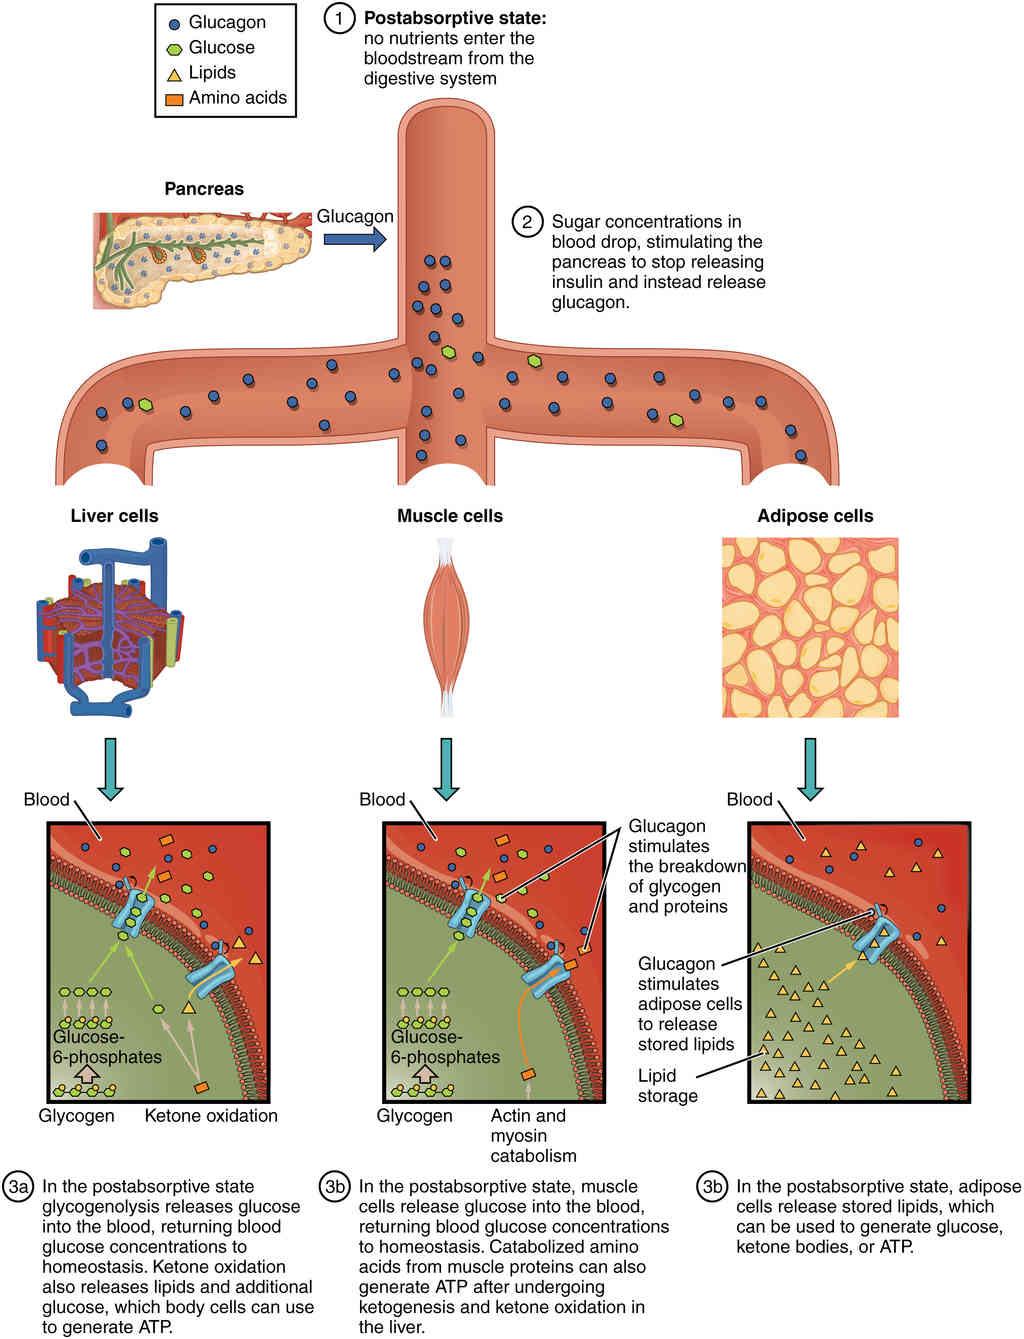

This page is under construction. For now, it is just a resource of the images found in the OpenStax Anatomy and Physiology Handbook. It wil slowly change into a revision tool. Each slide has a number. Use this to refer to the slide. When completed, it will have an unlabelled section, with labelled slides in parallel. On the unlabelled slides, write your answer and use the labelled slide to assess yourself. Keep track by also noting the number on each slide. Improvement at each attempt is important, more so than full marks on a first attempt.